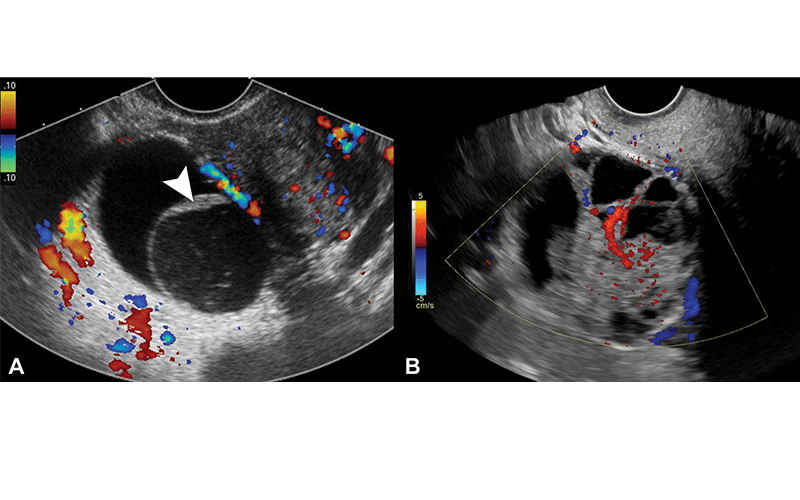

Representative transvaginal US images of nonclassic lesions; color Doppler blood flow with color bar signifies direction of flow. (A) Transverse color Doppler image of right adnexa depicts a multilocular cystic lesion with smooth septation (arrowhead) and no Doppler flow, compatible with a nonclassic lesion without blood flow. (B) Transverse color Doppler image of right adnexa depicts a multilocular cystic lesion with solid component and internal Doppler flow, compatible with a nonclassic lesion with blood flow.

Gupta et al, Radiology 2022; 000:1–8, @RSNA 2022